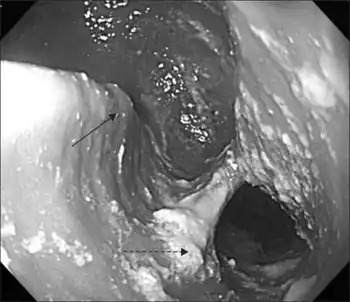

Endoscopic finding of Killian-Jamieson diverticulum,large diverticulum was noticed at 20 cm from incisor.